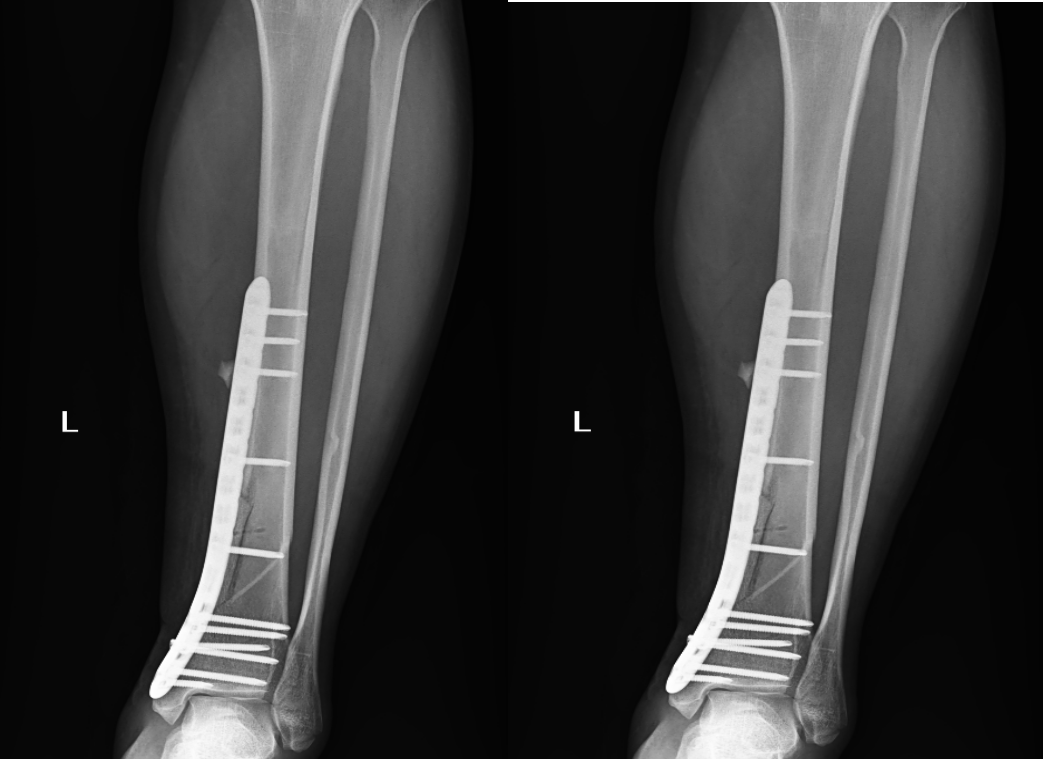

此次手术的成功,离不开八一医院外科医务人员的紧密协作。他们以高度的责任感和专业精神,及时解决了患者的燃眉之急,有效避免了病情恶化的风险。未来,八一医院外科将继续秉持创新精神,不断提升医疗技术水平,致力于为广大病患提供更加优质、高效的医疗服务。